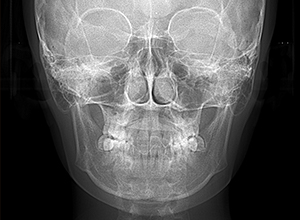

| X-Ray所見 | |

| セファロ所見 | 下顎頭はやや後方に位置しているが骨体部、下顎枝共に大きく上部構造体に対してバランスよく位置付いていた。中顔面は奥行きがあり下顔面高の高さは高くなかった。 |

| パノラマ所見 | 上顎両側第三大臼歯は欠損、下顎第三大臼歯は埋伏していた。 |